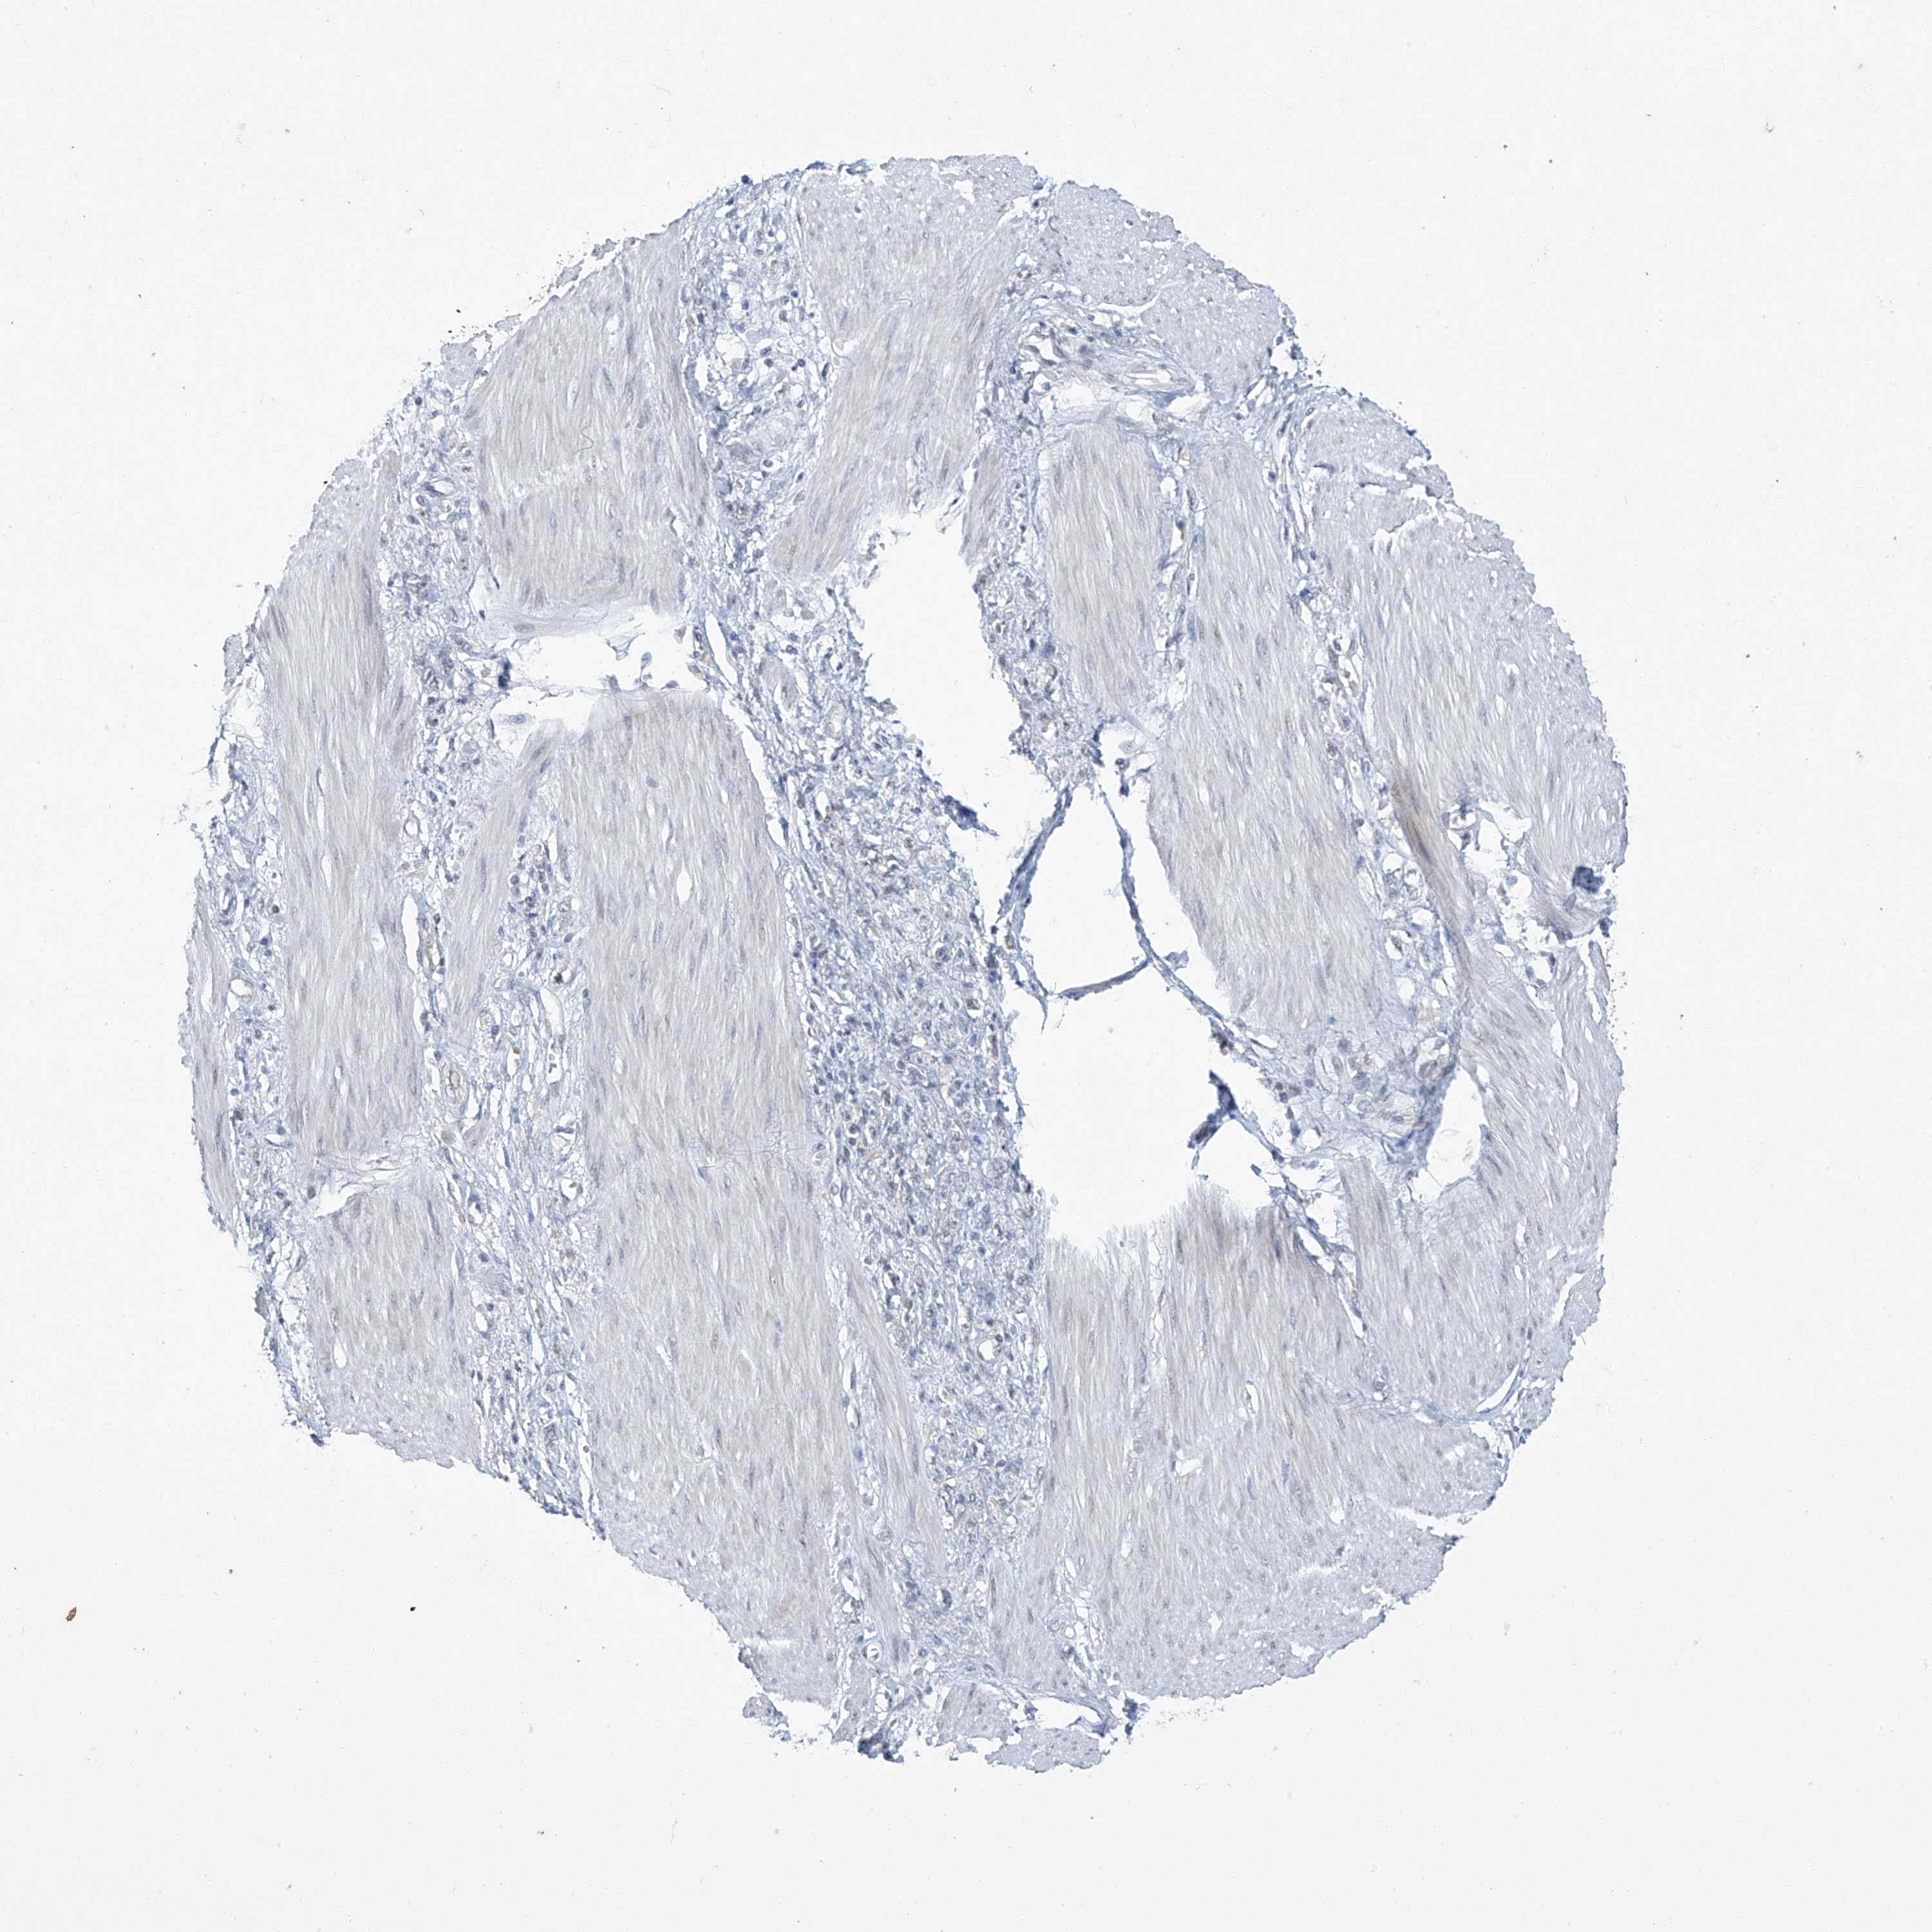

STOMACH CANCER - Protein expressioni

A mouse-over function shows sample information and annotation data. Click on an image to view it in a full screen mode. Samples can be filtered based on level of antibody staining by selecting one or several of the following categories: high, medium, low and not detected. The assay and annotation is described here.

Note that samples used for immunohistochemistry by the Human Protein Atlas do not correspond to samples in the TCGA dataset.

Antibody stainingi

Antibody staining in the annotated cell types in the current human tissue is reported as not detected, low, medium, or high, based on conventional immunohistochemistry profiling in selected tissues. This score is based on the combination of the staining intensity and fraction of stained cells.

Each image is clickable and will lead to virtual microscopy that enables deeper exploration of all samples and also displays staining intensity scores, fraction scores and subcellular localization as well as patient and tissue information for each sample.

Antibody HPA031730

Antibody HPA031731

Antibody HPA031734

Staining

High

Medium

Low

Not detected

Intensity

Strong

Moderate

Weak

Negative

Quantity

>75%

75%-25%

<25%

None

Location

Nuclear

Cytoplasmic/membranous

Cytoplasmic/membranous,nuclear

Adenocarcinoma, NOS